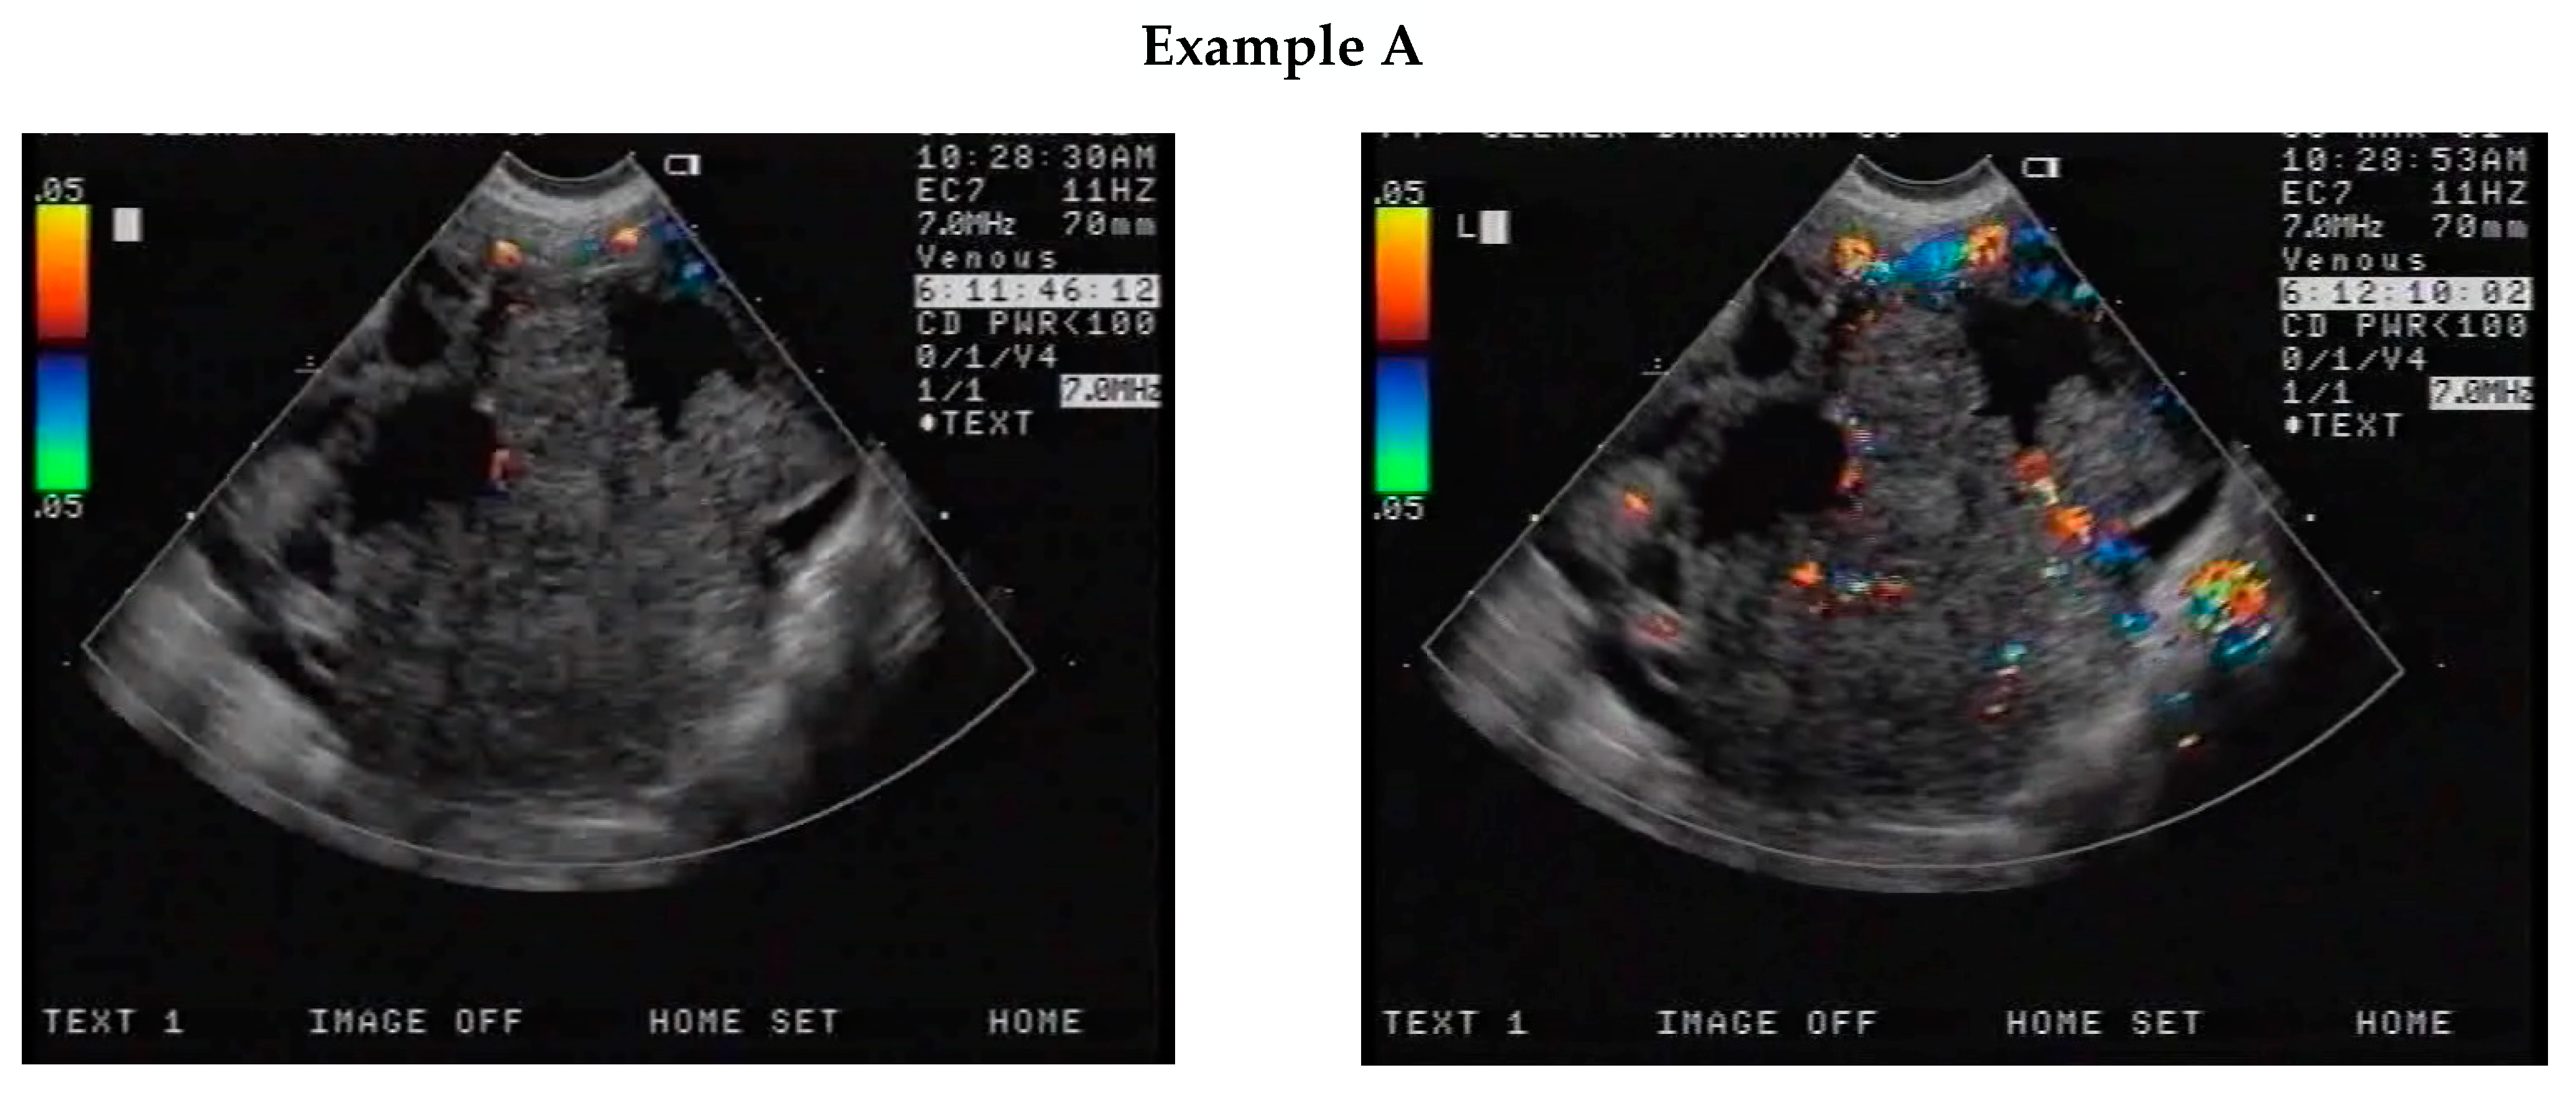

2.2. CEUS